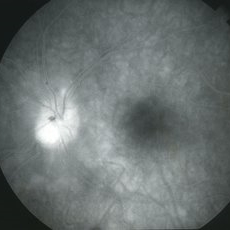

Toxocara Granuloma

Toxocara Granuloma

Feb 25 2013 by Henry J. Kaplan, MD

Toxocara granuloma of the optic nerve head.

Condition/keywords: ocular toxoplasmosis, toxocara granuloma, toxocariasis